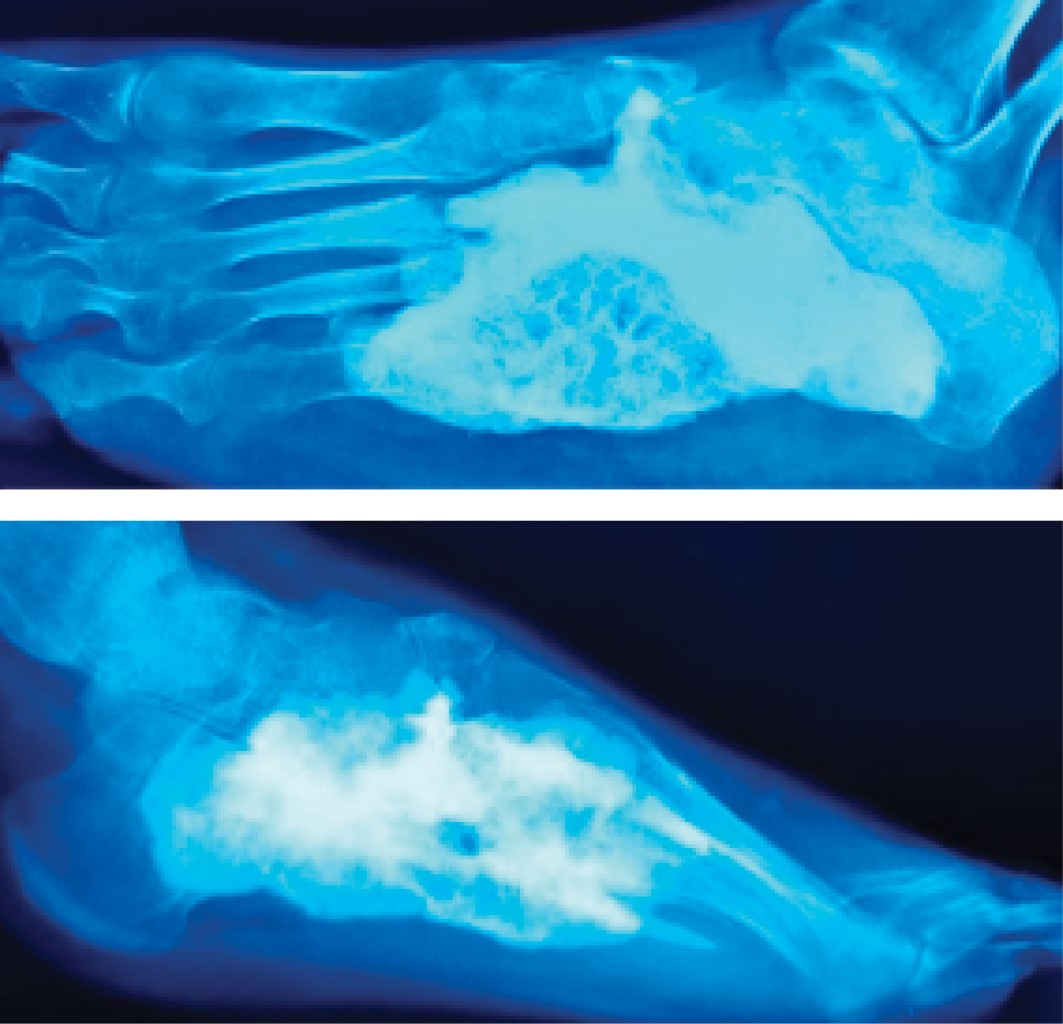

Aggressive chondroblastoma of the cuboid, unusual location. Case report and literature review

The case of a cuboid chondroblastoma in a 15-year-old woman is presented. This tumor presents an aggressive behavior which does not respond to treatment by curettage, bone grafting and adjuvant cryosurgery in the tissues affected by the tumor. The torpid evolution subsequently forces the need of a radical resection. Despite being classified as an aggressive benign tumor, a mention is made of the possibility of pulmonary metastases and local aggressiveness in some cases, such as that of this patient.

Figure 3

Figure 4